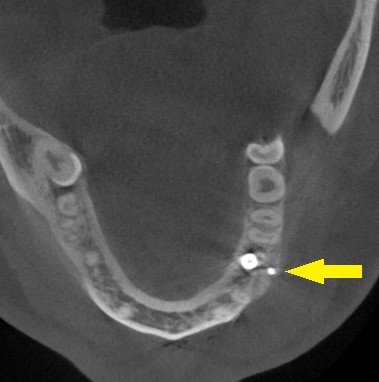

人工骨を使用しての骨造成術を併用して、インプラント埋入を行なうことで了承されましたので、本日、同手術を施行しました。

下の写真に手術前後のCTを示します。